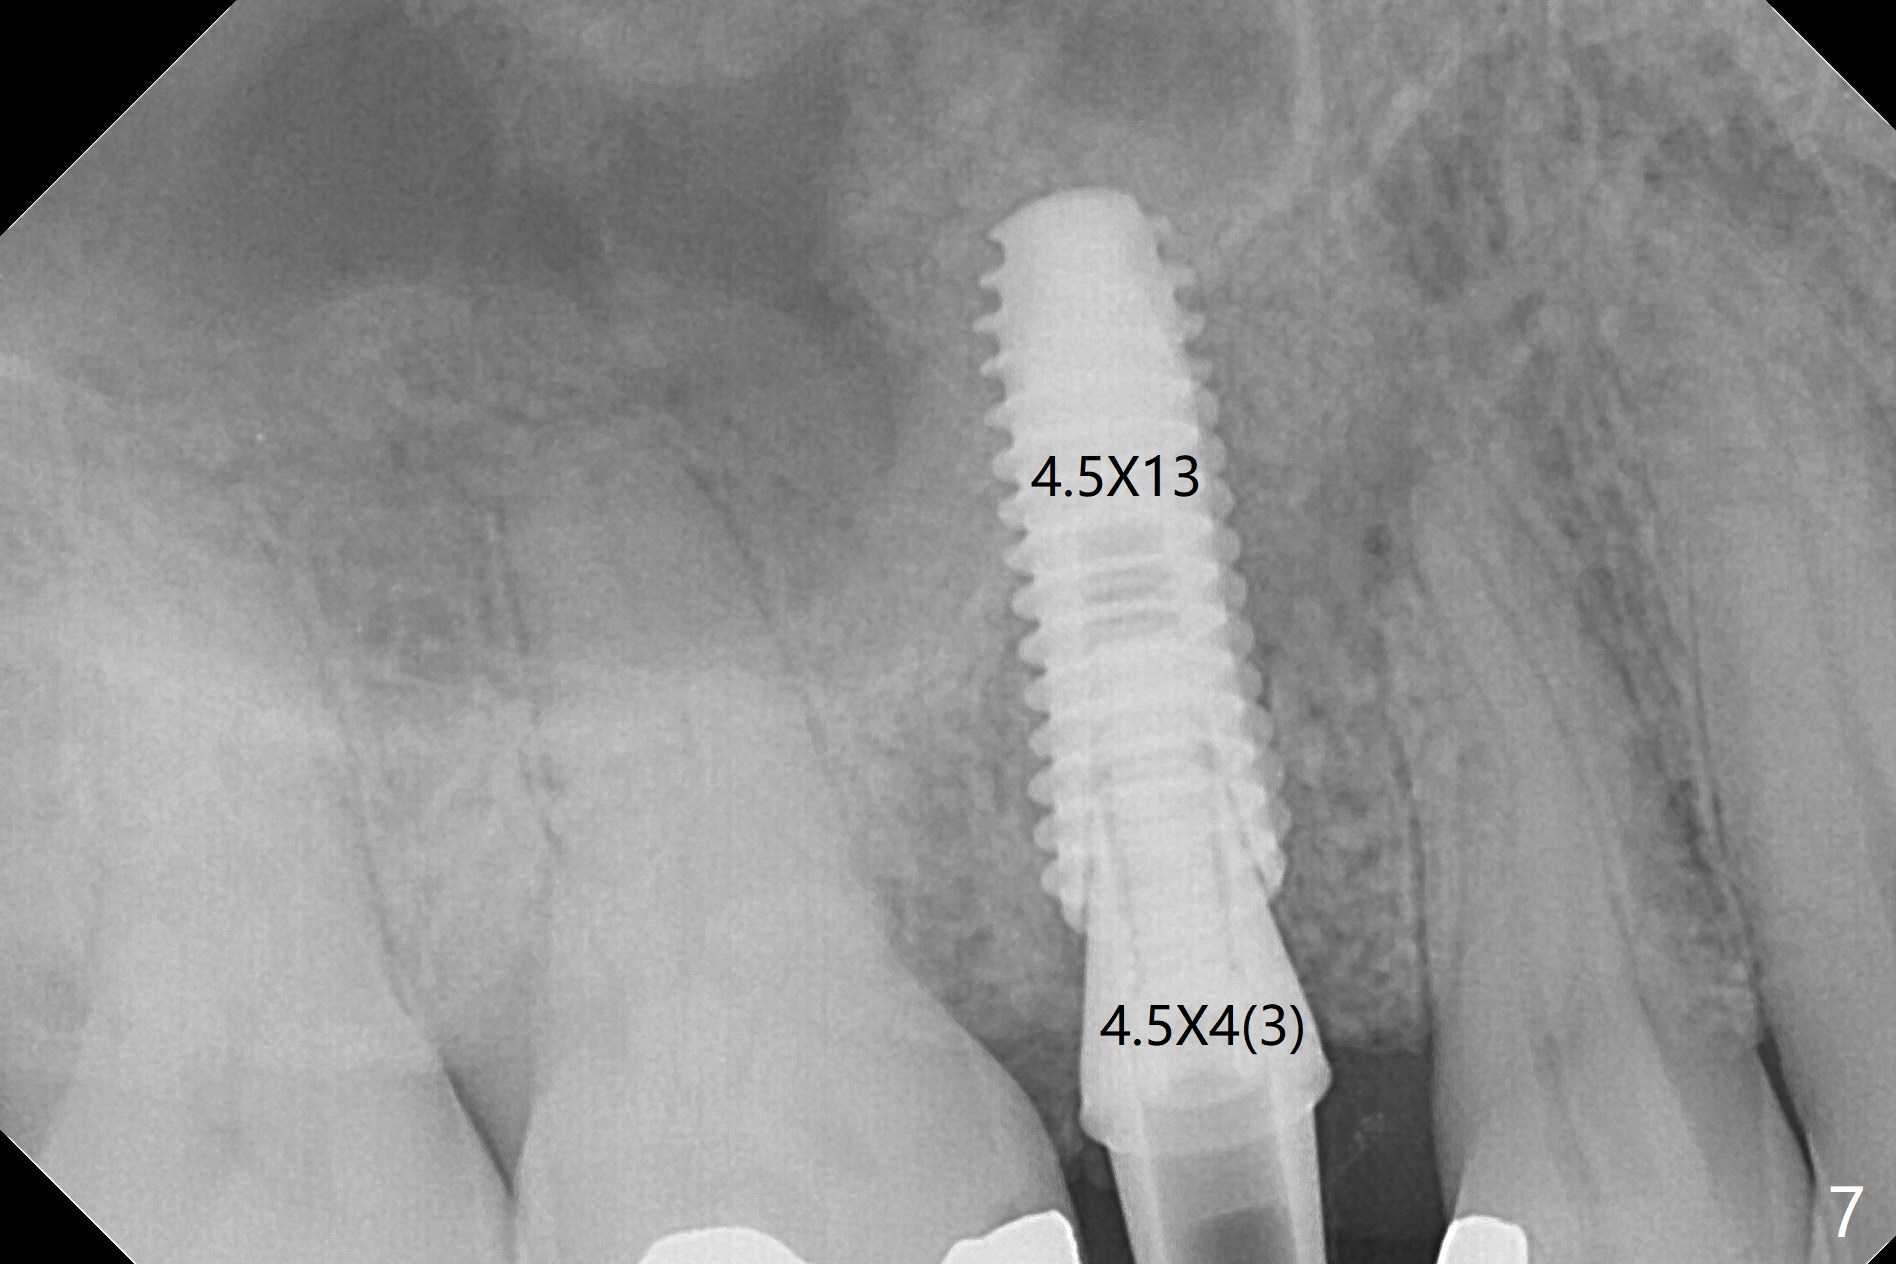

The 48-year-old man agrees to extract the tooth #4 with buccal and palatal fistulae (Fig.1,2 >) and large PARL (Fig.3 *) because of purulent discharge. The large post (Fig.3 P) is most likely associated with a longitudinal fracture. The latter is not noted until postop (Fig.4 <). Intraop finding is large amount of granulation tissue removed from the mesial apical region (Fig.3,5 *). With 10.5 mm offset, Sinus Approach Drill (19 mm) is estimated too short for sinus lift after 3x8.5 mm drill. Without careful repeated check, 2.2x10 and 2.2x11.5 mm drills are used. The sinus floor is perforated, but the membrane seems to be intact. The perforation is too small to insert PRF, but alright for allograft. Then nose blowing test shows that the sinus membrane is perforated, which seems to be repaired after placement of 2 pieces of PRF membrane, followed by another round of allograft (Fig.5 G), which is lifted by a 4x10 mm IS dummy implant. Before placement of a 4.5x11.5 mm final UF implant, allograft is placed in the 3 defective bony areas mentioned above, including the apical mesial one (Fig.6 *). But the final UF implant seems too short with non-satisfactory torque. The latter appears to be solved with the increased length of the implant (Fig.7). The gingiva around the provisional (P) is healthy without fistulae buccal (Fig.8) or palatal 17 days postop (Fig.9). A new abutment with 1 mm longer cuff is seated completely 5.5 months postop (Fig.10 < (no gap), as compared to Fig.7). The lower portion of the mesial defect seems to have been repaired (Fig.11 arrow, as compared to Fig.7). The bone in the sinus seems stable 1.5 years postop (Fig.12). There is no crestal bone loss 4 months post cementation (Fig.13). Return to Upper Premolar Immediate Implant, Trajectory II Xin Wei, DDS, PhD, MS 1st edition 09/27/2019, last revision 04/12/2021